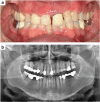

Orthodontic forces have been reported to significantly increase nicotine-induced periodontal bone loss. At present, however, it is unknown, which further (side) effects can be expected during orthodontic treatment at a nicotine exposure corresponding to that of an average European smoker. 63 male Fischer344 rats were randomized in three consecutive experiments of 21 animals each (A/B/C) to 3 experimental groups (7 rats, 1/2/3): (A) cone-beam-computed tomography (CBCT); (B) histology/serology; (C) reverse-transcription quantitative real-time polymerase chain reaction (RT-qPCR)/cotinine serology-(1) control; (2) orthodontic tooth movement (OTM) of the first and second upper left molar (NiTi closed coil spring, 0.25 N); (3) OTM with 1.89 mg·kg-1 per day s.c. of L(-)-nicotine. After 14 days of OTM, serum cotinine and IL-6 concentration as well as orthodontically induced inflammatory root resorption (OIIRR), osteoclast activity (histology), orthodontic tooth movement velocity (CBCT, within 14 and 28 days of OTM) and relative gene expression of known inflammatory and osteoclast markers were quantified in the dental-periodontal tissue (RT-qPCR). Animals exposed to nicotine showed significantly heightened serum cotinine and IL-6 levels corresponding to those of regular European smokers. Both the extent of root resorption, osteoclast activity, orthodontic tooth movement and gene expression of inflammatory and osteoclast markers were significantly increased compared to controls with and without OTM under the influence of nicotine. We conclude that apart from increased periodontal bone loss, a progression of dental root resorption and accelerated orthodontic tooth movement are to be anticipated during orthodontic therapy, if nicotine consumption is present. Thus patients should be informed about these risks and the necessity of nicotine abstinence during treatment.